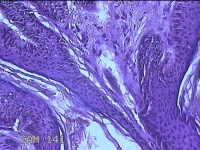

左侧会阴部结节

性别

女

年龄

43岁

临床诊断

皮肤良性肿瘤

一般病史

发现右侧会阴部结节3年余。

标本名称

大体所见

灰白粉红色带皮肤结节0.8x0.7x0.3cm一个,表面光滑,切开结节呈实性,切面灰白粉红色,质韧。

图2